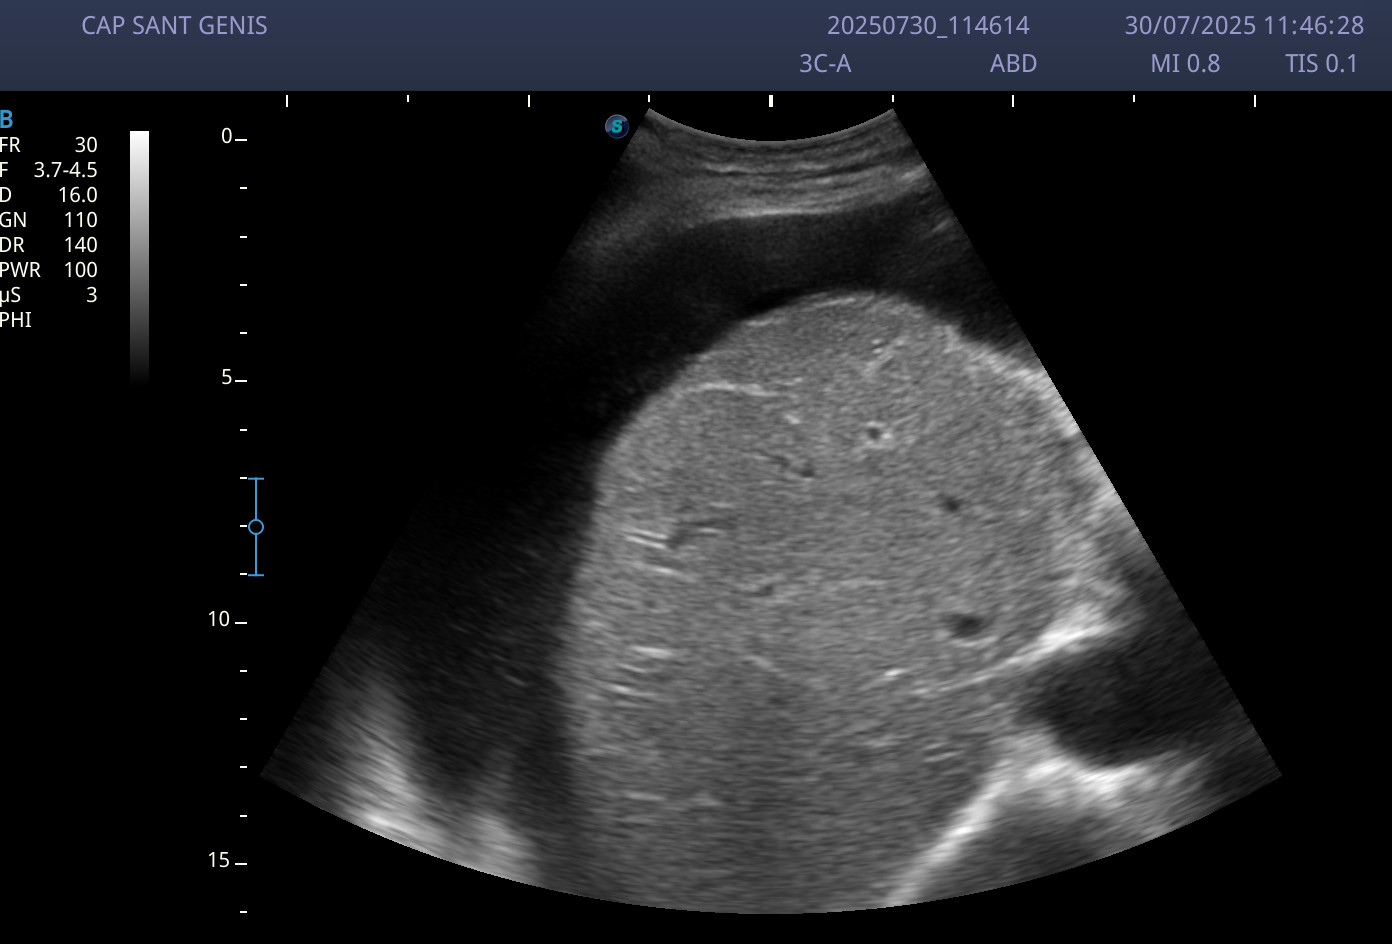

Ecografía abdominal: abundante ascitis perivisceral, y sobre todo a nivel perihepático.